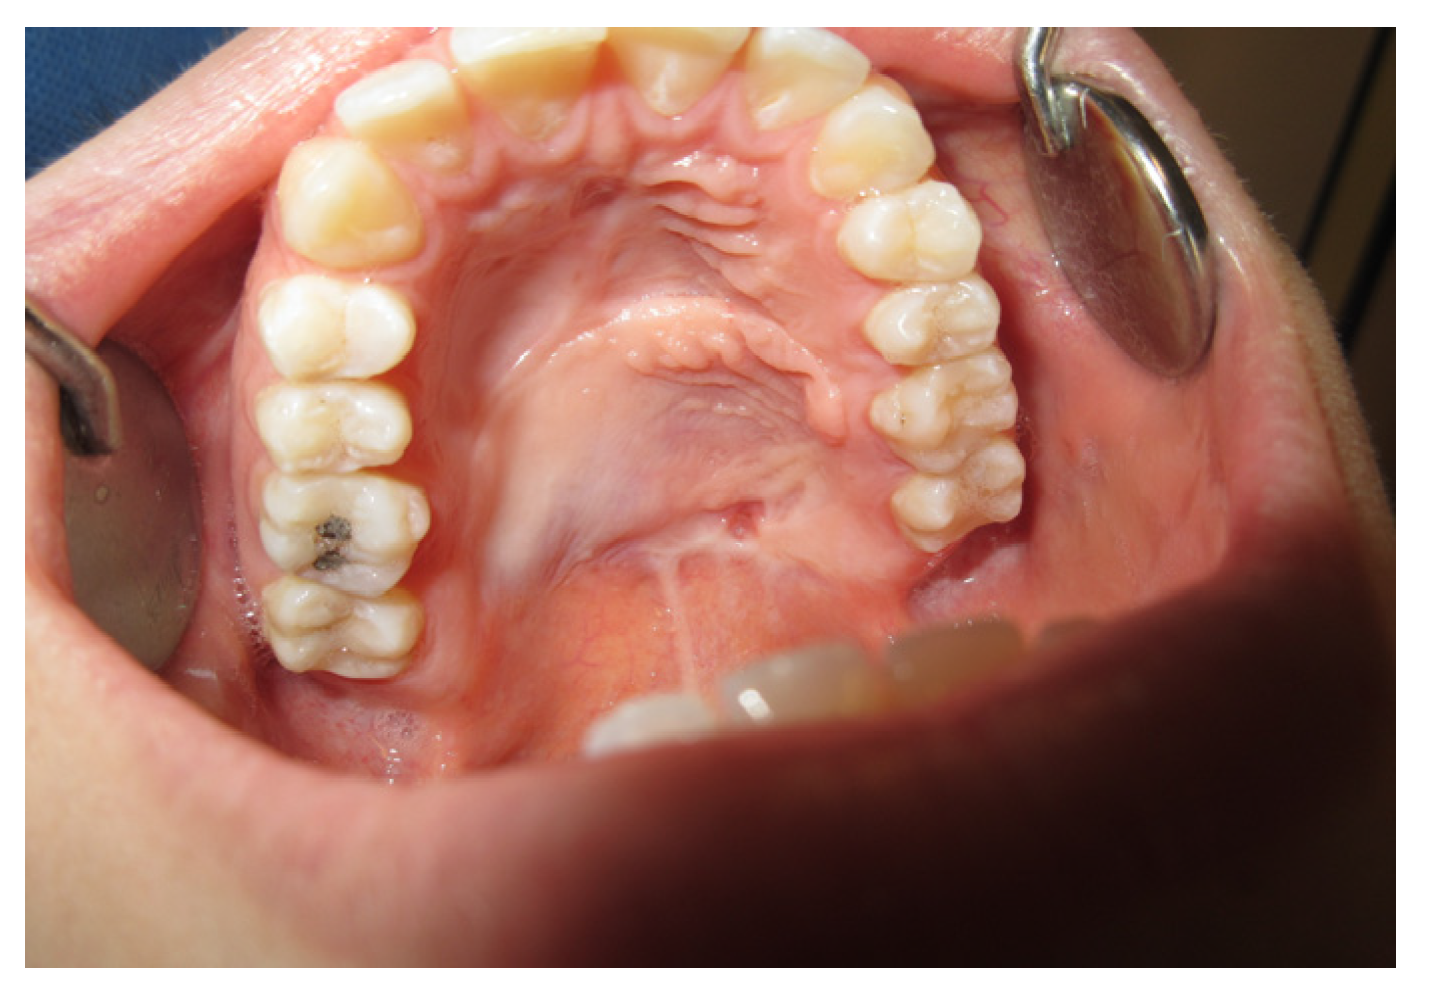

3.1.4. Case 4: P.M.A.

| P.M.A | X | * | 5 | 5 |